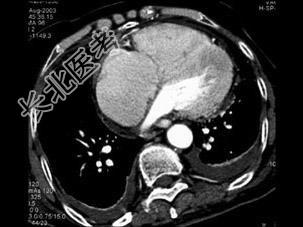

- 单项选择题男,38岁, 反复咳嗽、咳痰伴发热15年余,痰结核菌素试验(—), 结合CT图像,最可能的诊断是 ( )